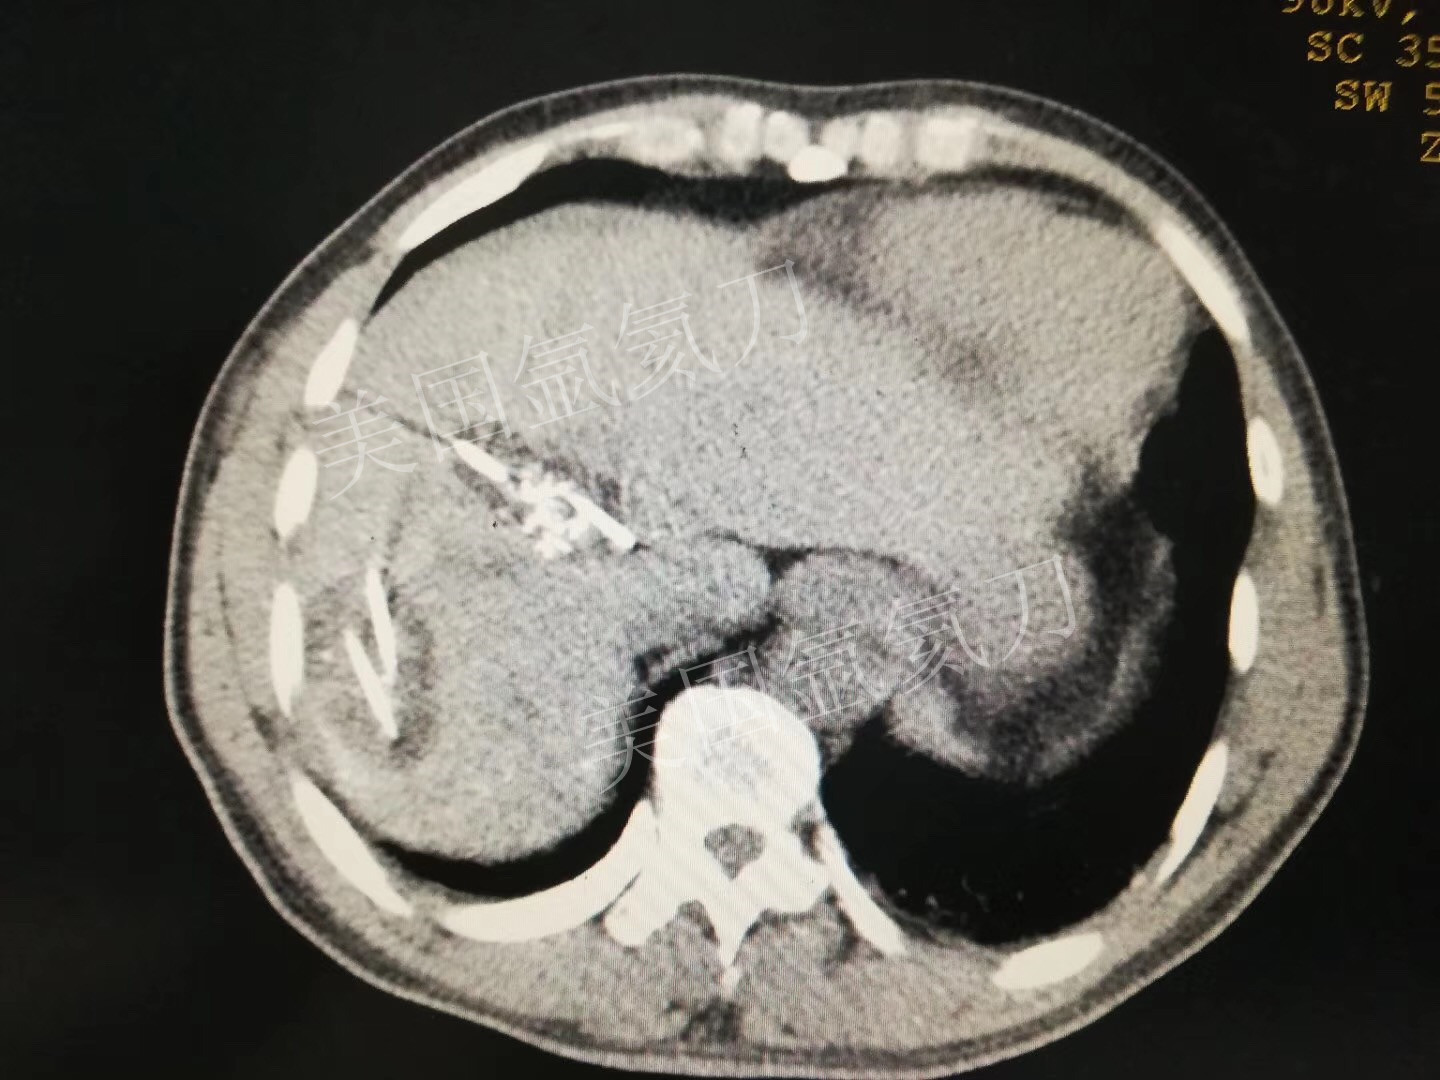

氩氦刀消融两个3公分介入后病灶,疗效确切!